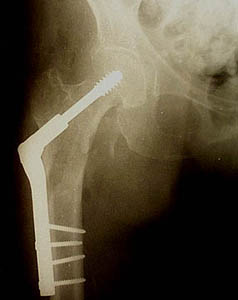

Men spreekt dan van een subtrochantere femurfractuur. De DHS of dynamic hip screw bestaat in feite uit twee componenten.We onderscheiden een stevige schroef die vanuit de laterale cortex van de schacht in de kop grijpt en een plaat die op de schroef aangrijpt en het geheel aan de schacht fixeert.

Het speciale kenmerk van een DHS is de mogelijkheid van de kop nagel om te glijden en dus te collaberen in de plaat. Dit is een enorm voordeel vanuit biomechanisch standpunt en voorkomt zeer vervelende en ernstige complicaties zoals “cut-out” en intra-articulaire perforatie van de schroef in het gewricht.

De ingreep wordt uitgevoerd op de tractietafel. Dit is een speciale orthopedische tafel waar een tractie device op aangebracht is. Hierdoor kan de breuk goed gereduceerd worden. De operatie gebeurt via een incisie die ongeveer 15-20 cm lang is en die zuiver lateraal (d.w.z. aan de buitenkant van de dij) gelegen is. De operatieduur bedraagt ongeveer 45 minuten.